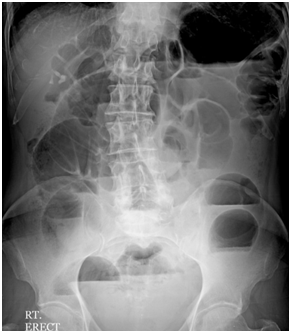

A 35year old female presented with features of acute intestinal obstruction with colicky abdominal pain, distension and bilious vomiting for last two days. She was having history of recurrent episodes of bilious vomiting and loss of appetite for past 3 months. She was also experiencing repeated episodes of colicky abdominal pain which used to be relieved after taking anti-spasmodic medications. She had no prior history of abdominal surgery. Clinical examination revealed dehydration, anicteric, afebrile, blood pressure of 110/60 mmHg, abdominal distention, hyper-peristaltic bowel sounds, abdominal hypertympanism, and tenderness in the hypogastrium, characterizing intestinal occlusion. The biochemical parameters were within normal limits. Abdominal radiograph in erect position revealed multiple air-fluid levels in step ladder pattern without any free gas (Figure 1). The patient was resuscitated for correction of fluid deficit and dyselectrolemia. As the patient was in acute intestinal obstruction for the last two days, so the patient was planned for emergency laparotomy without doing the contrast studies.